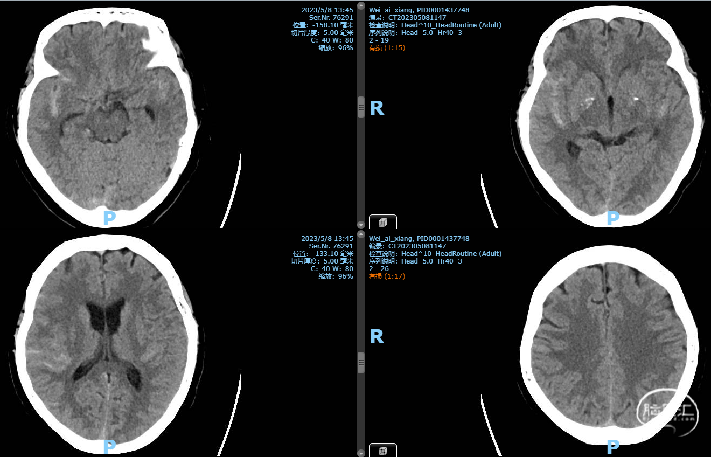

2023-05-10 术后CT

Nuva 4.0x24,非常顺滑到位,稍维持张力,自主打开好;半释放保护瘤颈,填入泰杰3d36、Axium2d24、1.5x4;微导丝按摩支架。

手术过程

手术材料

通路:8F指引导管、 Navien 072-115中间导管

微导管微导丝:Echelon10微导管,Synchro-14微导丝,泰杰微导管

弹簧圈:泰杰3mm*6cm 3D、ev3 Axium 2mm*4cm 、ev3 Axium 1.5mm*4cm

支架:Nuva血流导向密网支架TJED-D-4.5-18

封堵系统:动脉缝合器、压迫器

一般项目:男,57,因“检查发现颅内动脉瘤6年”于2023-5-8 入院。

病例特点:患者诉6年前因头晕至广西医科大学一附院行头部CTA检查发现颅内动脉瘤,未予以处理。

既往史:2014年因蛛网膜下腔出血在南宁红会医院住院,具体治疗不详。

NS(-) 。

辅查:2017年广西医科大学一附院头部CTA提示左侧椎动脉V4段动脉瘤。

诊疗计划

nuva 密网支架植入

TJED-D-5.0-35(4.5x49),XT27输送很涩,释放过程控制好张力支架还是不断回缩,考虑直径过小,维持微导管较大张力释放,收尾稍减张释放,支架打开好。

动脉瘤内造影剂滞留

支撑系统:中天医疗6F远端通路导管、Neuron MAX 6F 088导引导管

微导管/导丝:Synchro-14微导丝、Excelsior XT27导管

支架:Nuva密网支架TJED-D-5.0-35(4.5x49)

术后第一天